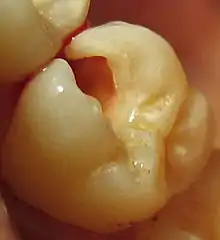

The process of preparation usually involves cutting the tooth with a rotary dental handpiece and dental burrs, a dental laser, or through air abrasion (or in the case of atraumatic restorative treatment, hand instruments), to make space for the planned restorative materials and to remove any dental decay or portions of the tooth that are structurally unsound. If permanent restoration cannot be carried out immediately after tooth preparation, temporary restoration may be performed.

The prepared tooth, ready for placement of restorative materials, is generally called a tooth preparation. Materials used may be gold, amalgam, dental composites, glass ionomer cement, or porcelain, among others.

Preparations may be intracoronal or extracoronal. Intracoronal preparations are those which serve to hold restorative material within the confines of the structure of the crown of a tooth. Examples include all classes of cavity preparations for composite or amalgam as well as those for gold and porcelain inlays. Intracoronal preparations are also made as female recipients to receive the male components of removable partial dentures. Extracoronal preparations provide a core or base upon which restorative material will be placed to bring the tooth back into a functional and aesthetic structure. Examples include crowns and onlays, as well as veneers.

In preparing a tooth for a restoration, a number of considerations will determine the type and extent of the preparation. The most important factor to consider is decay. For the most part, the extent of the decay will define the extent of the preparation, and in turn, the subsequent method and appropriate materials for restoration.

Another consideration is unsupported tooth structure. When preparing the tooth to receive a restoration, unsupported enamel is removed to allow for a more predictable restoration. While enamel is the hardest substance in the human body, it is particularly brittle, and unsupported enamel fractures easily.